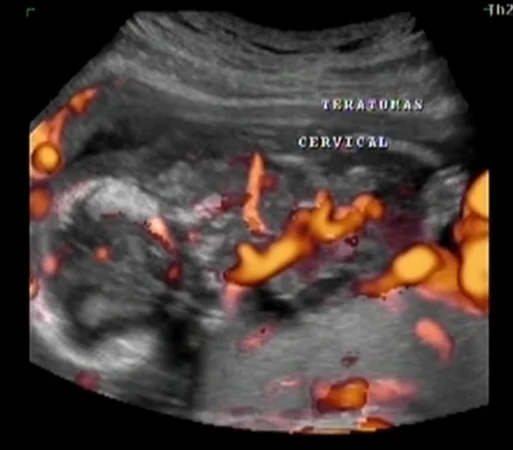

• U quái vùng cổ thai nhi (Cervical Teratoma)